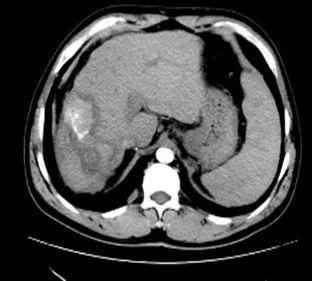

2. 肺部病灶治疗前后核磁对比:

肺部转移病灶在用药后2个月明显缩小,4个月后病灶基本消失。

治疗前

治疗2个月

治疗4个月

治疗6个月

治疗16个月